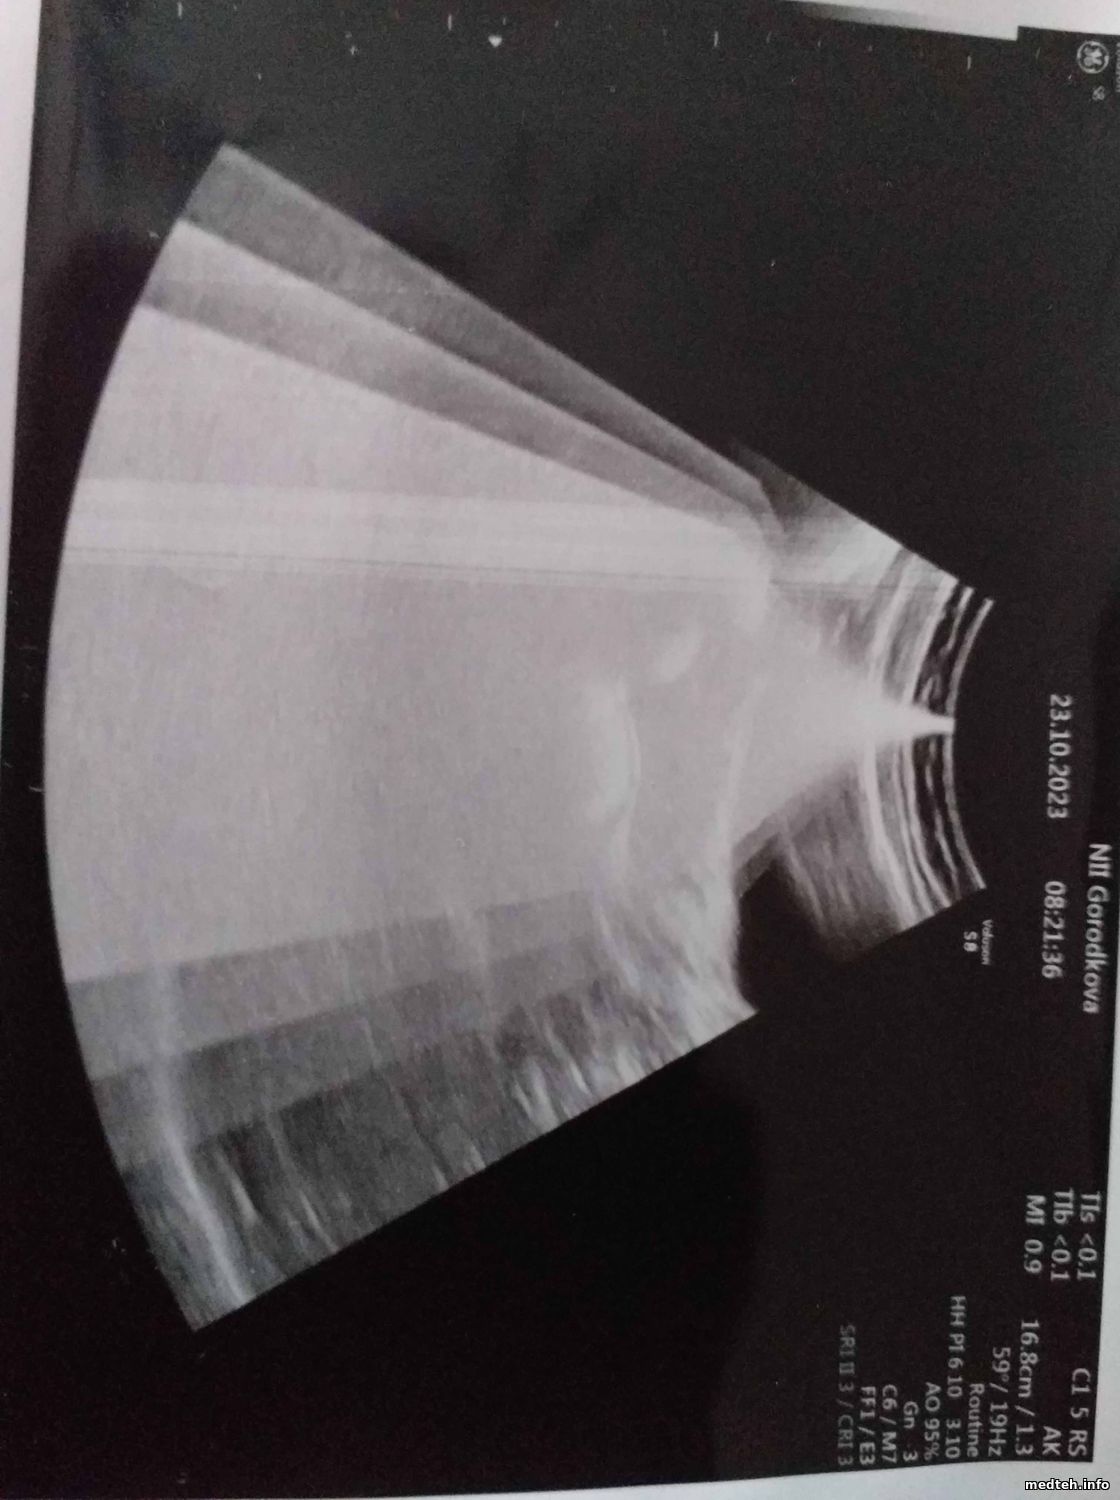

Добрый день.

Подскажите, пожалуйста, почему на экране могли появится такие помехи:

8008131.jpg (162.1 Kb) · 3192639.jpg (162.2 Kb)

ivobldebts, hi.

DBF128 board is defective.